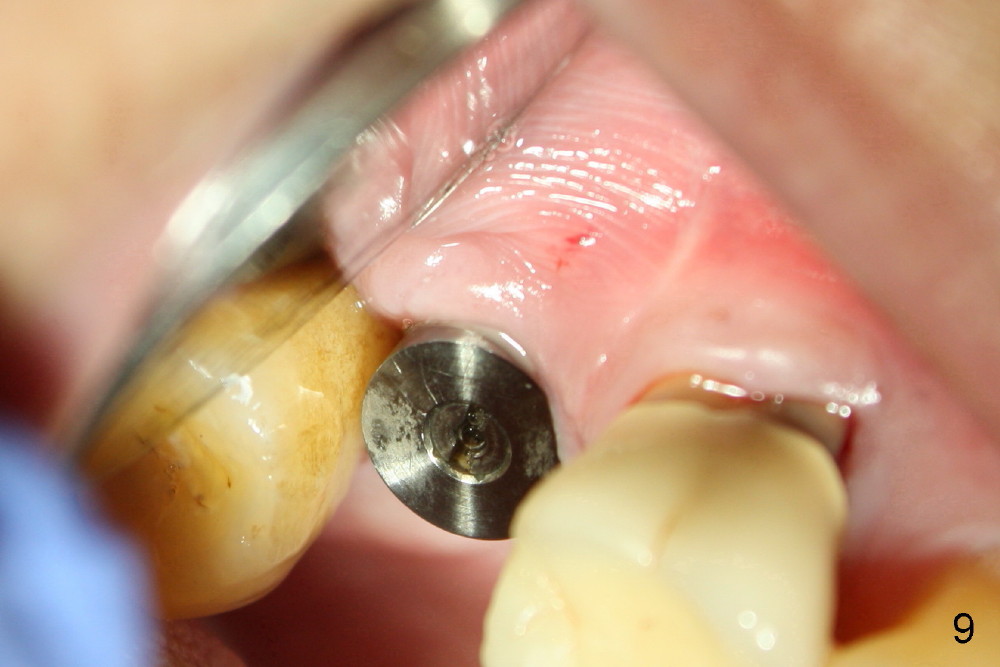

The 60-year-old man is a bruxer. All of the three upper right molars are nonsalvageable (Fig.1). Since #2 is symptomatic, it is planned to be extracted and restored first. As expected, there is severe alveolar destruction (single large socket), while the base bone is solid. A series of tapered osteotomes (2-5 mm) are used to create osteotomy in the base bone (gaining 4 mm into new bone), followed by 4.5x20 mm tap at the depth of 17 mm from the gingival margin (Fig.2). Then the depth is adjusted to 14 mm; the bone expansion and osteotomy continue until using 7 mm tap with good binding to the bone (Fig.3). A 7x14 mm implant is placed with insertion torque more than 60 Ncm (Fig.4). No bone graft is used for sinus lift considering sinus membrane perforation. The buccal flap is raised to reveal bony defect, which is covered by Osteogen (a synthetic bone graft) and then collagen membrane (Fig.6 *). Five days postop, the membrane undergoes a type of transformation (Fig.7 *) leading to a gingival tissue (Fig.8 *, 18 days postop). By 3 months, the gingiva has normal appearance (Fig.9), while the implant seems to be osteointegrated (Fig.10). Once the infected source is removed, our body has potential to regenerate.